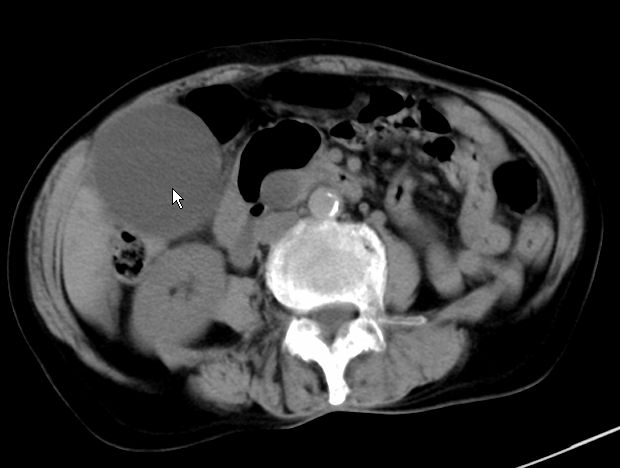

以下是引用zjzjr在2008-12-16 12:49:00的发言:[br]肝内外胆管全程扩张,胆囊明显增大,未见占位征像.建议mrcp.

以下是引用jiangjing在2008-12-16 13:19:00的发言:[br]肝内外胆管全程扩张,胆囊明显增大,扩张胆总管下段径较中上段小,未见胰管扩张,提示胆总管远端梗阻伴感染.建议增强及mrcp 检查

以下是引用朱亮在2008-12-16 12:54:00的发言:[br]胆总管远端应薄层扫描 胆总管逐渐变细 考虑胆系慢性炎症